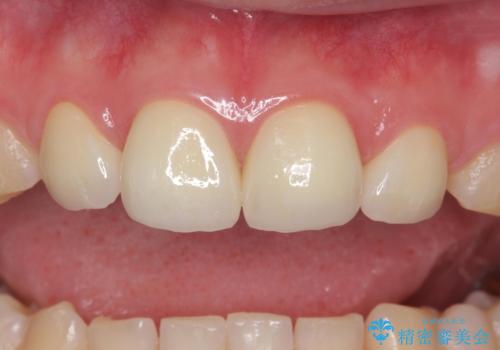

矯正治療とかぶせ物での治療どちらともご提案したところ、かぶせ物での治療をご希望されたためクラウンでの審美性回復を試みることとなりました。

今回のように、元の歯が小さすぎる場合は矯正治療での審美性回復が難しいことがあります。

形のイメージを反映させた仮歯を調整し、技工士さんと連携して製作したため口元に調和した非常に審美的なクラウンを装着することができました。